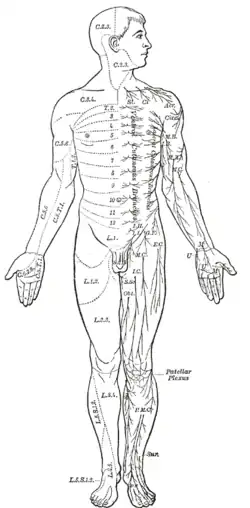

The human nervous system | |

In biology, the nervous system is the highly complex part of an animal that coordinates its actions and sensory information by transmitting signals to and from different parts of its body. The nervous system detects environmental changes that impact the body, then works in tandem with the endocrine system to respond to such events.[1] Nervous tissue first arose in wormlike organisms about 550 to 600 million years ago. In vertebrates, it consists of two main parts, the central nervous system (CNS) and the peripheral nervous system (PNS). The CNS consists of the brain and spinal cord. The PNS consists mainly of nerves, which are enclosed bundles of the long fibers, or axons, that connect the CNS to every other part of the body. Nerves that transmit signals from the brain are called motor nerves (efferent), while those nerves that transmit information from the body to the CNS are called sensory nerves (afferent). The PNS is divided into two separate subsystems, the somatic and autonomic nervous systems. The autonomic nervous system is further subdivided into the sympathetic, parasympathetic and enteric nervous systems. The sympathetic nervous system is activated in cases of emergencies to mobilize energy, while the parasympathetic nervous system is activated when organisms are in a relaxed state. The enteric nervous system functions to control the gastrointestinal system. Nerves that exit from the brain are called cranial nerves while those exiting from the spinal cord are called spinal nerves.

Anatomy in vertebrates

The nervous system of vertebrates (including humans) is divided into the central nervous system (CNS) and the peripheral nervous system (PNS).[16] The CNS is the major division, and consists of the brain and the spinal cord.[16] The spinal canal contains the spinal cord, while the cranial cavity contains the brain. The CNS is enclosed and protected by the meninges, a three-layered system of membranes, including a tough, leathery outer layer called the dura mater. The brain is also protected by the skull, and the spinal cord by the vertebrae.

The peripheral nervous system (PNS) is a collective term for the nervous system structures that do not lie within the CNS.[17] The large majority of the axon bundles called nerves are considered to belong to the PNS, even when the cell bodies of the neurons to which they belong reside within the brain or spinal cord. The PNS is divided into somatic and visceral parts. The somatic part consists of the nerves that innervate the skin, joints, and muscles. The cell bodies of somatic sensory neurons lie in dorsal root ganglia of the spinal cord. The visceral part, also known as the autonomic nervous system, contains neurons that innervate the internal organs, blood vessels, and glands. The autonomic nervous system itself consists of two parts: the sympathetic nervous system and the parasympathetic nervous system. Some authors also include sensory neurons whose cell bodies lie in the periphery (for senses such as hearing) as part of the PNS; others, however, omit them.[18]

Even mammals, including humans, show the segmented bilaterian body plan at the level of the nervous system. The spinal cord contains a series of segmental ganglia, each giving rise to motor and sensory nerves that innervate a portion of the body surface and underlying musculature. On the limbs, the layout of the innervation pattern is complex, but on the trunk it gives rise to a series of narrow bands. The top three segments belong to the brain, giving rise to the forebrain, midbrain, and hindbrain.[24]